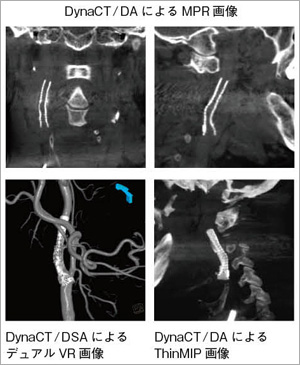

安価 ワタナベ 新潟大学医歯学総合病院における頭部領域でのDynaCTの臨床経験 歯科学の詳細情報

新潟大学医歯学総合病院における頭部領域でのDynaCTの臨床経験。研究の業績 | 大阪医科大学 形成外科学 教授 上田 晃一。新潟大学医歯学総合病院における頭部領域でのDynaCTの臨床経験。結わえる 寝かせ玄米小豆黒米十穀米もち麦16個セット酵素玄米。